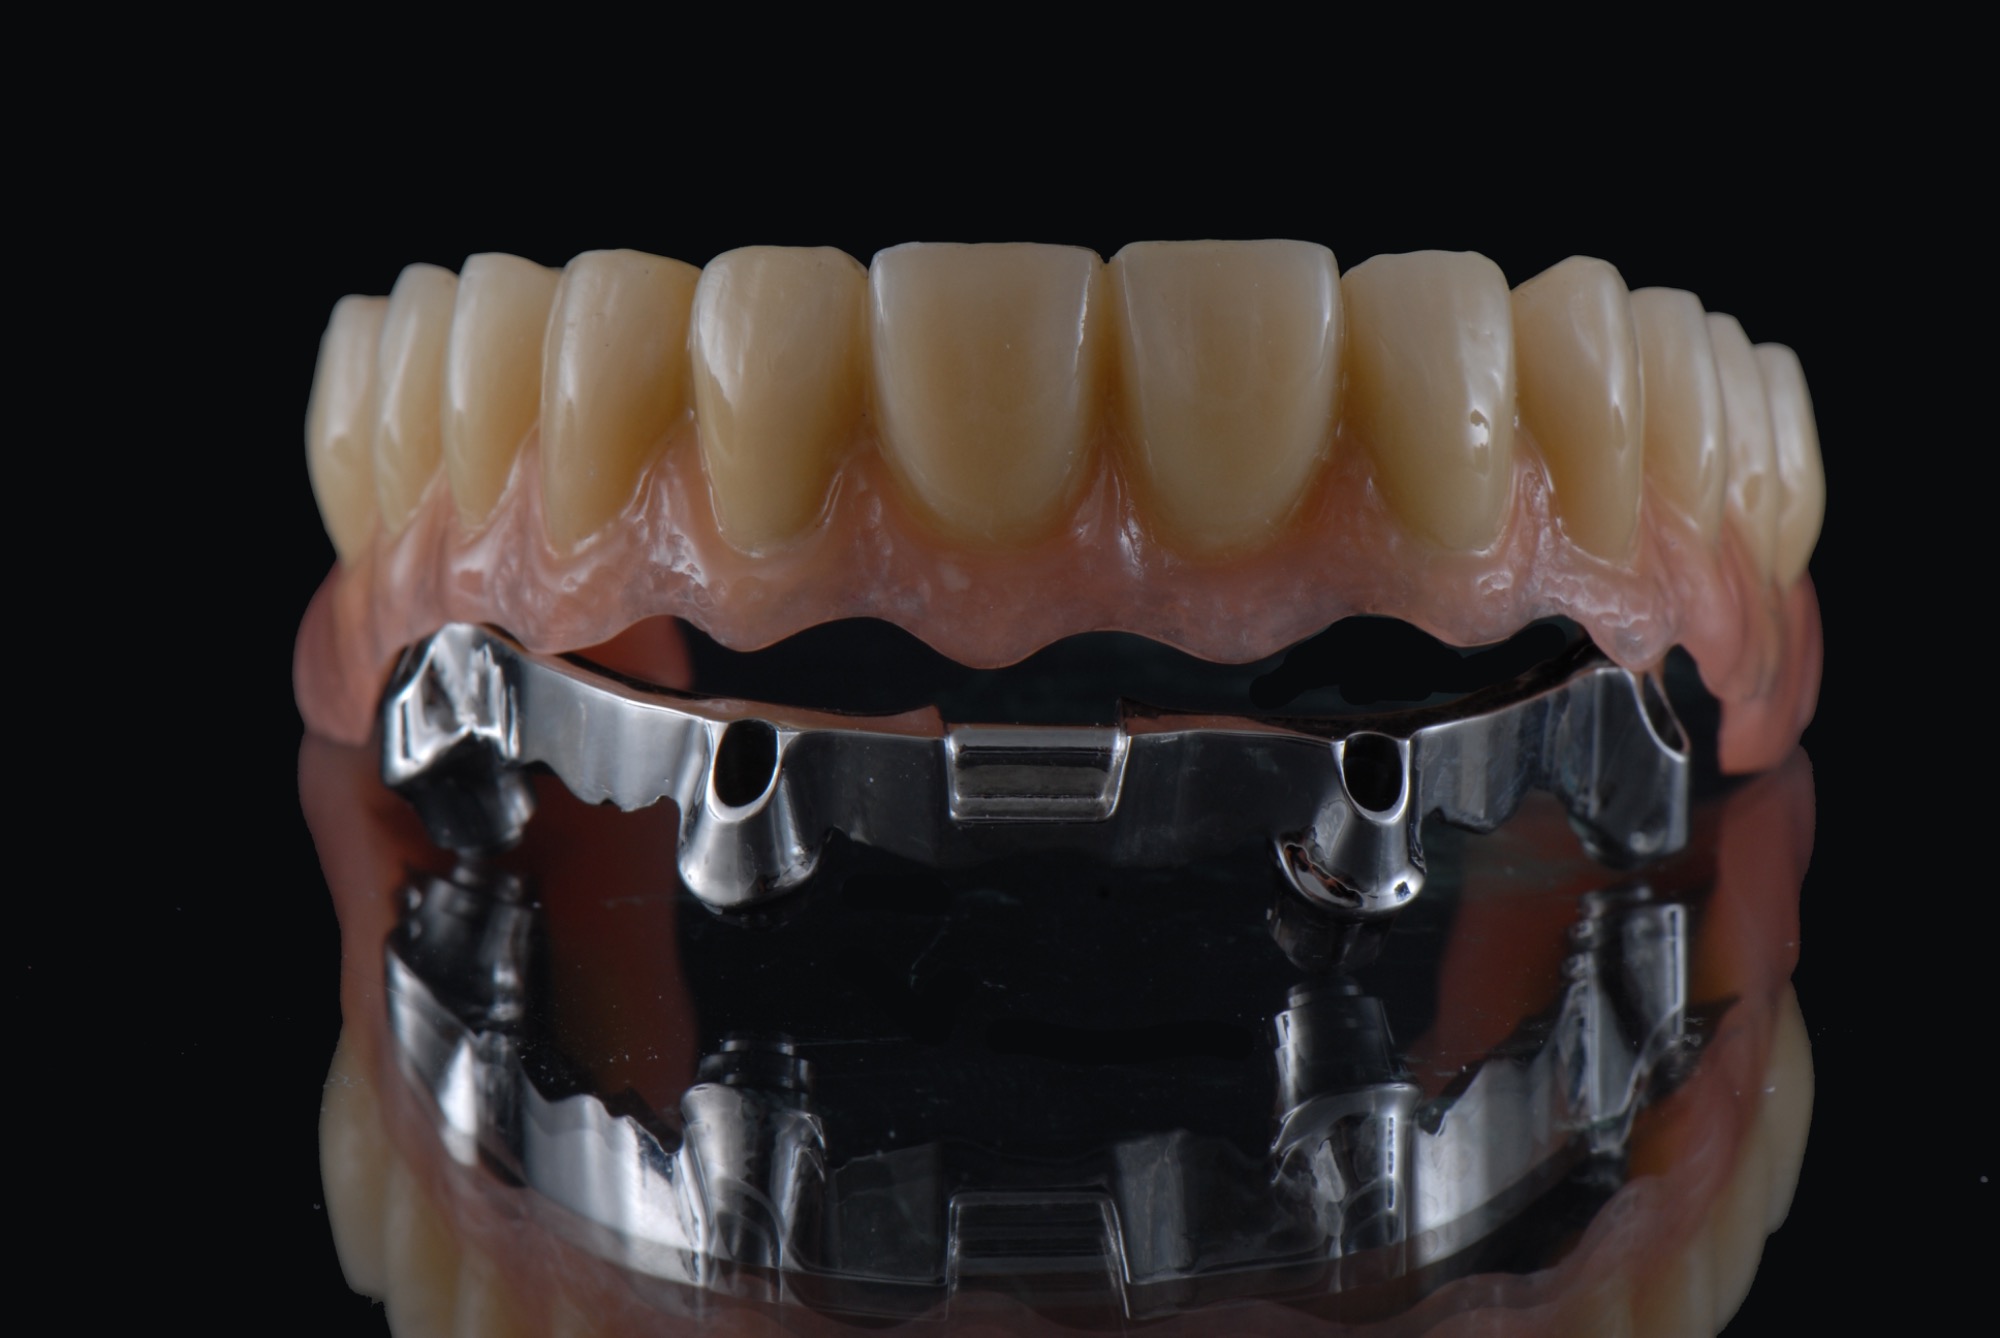

Implantsteg verankerte Brücke. Für den Patienten abnehmbar, aber der Tragekomfort von festen Zähnen.